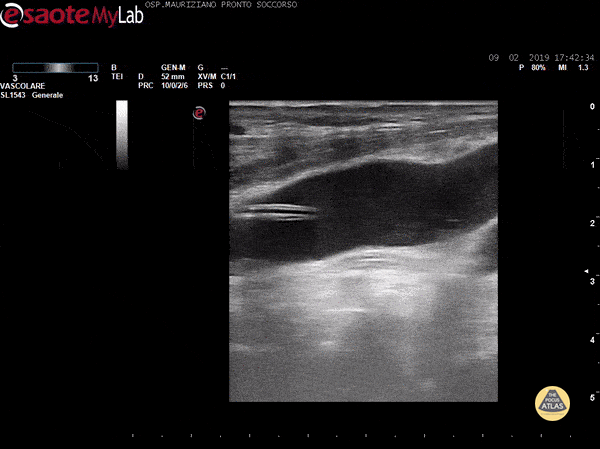

Vascular - CVC kinking in IJV

After a troubled implant (Seldinger wire got somehow stuck) there was normal IV dripping and normal blood reflux after positioning IV bottle below the patient. However, no flush in AD was visible. We scanned to find a 180° degrees kinking in IJV just below insertion site . Dr. Garrone